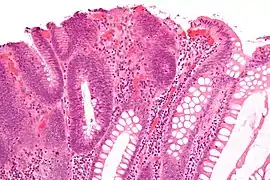

| Endoscopic image of sigmoid colon of patient with familial adenomatous polyposis | |